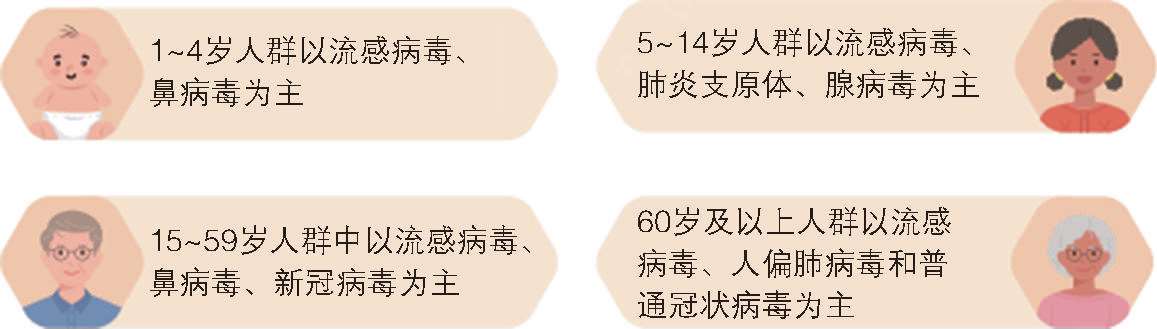

虽然大多数人群普遍易感,但5岁以下儿童、65岁及以上老年人是呼吸道感染性疾病的高危人群。